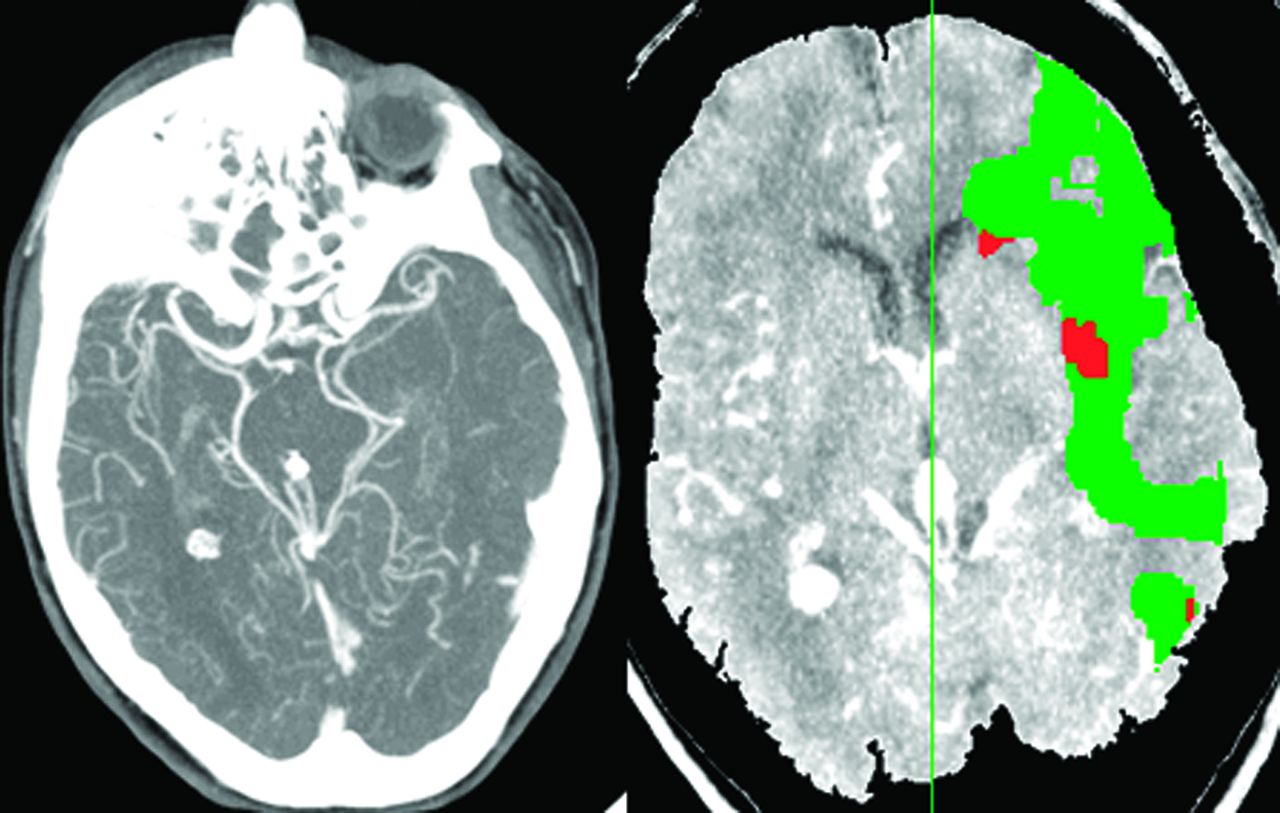

Diffusion-weighted成像(驾车)和perfusion-weighted MRI(预警指示器)是广泛使用的核磁共振成像模式,提供有价值的信息焦点脑缺血的组织特点和流动的微循环。17异常的表观扩散系数(ADC)在缺血性脑区醉酒驾车和组织灌注在预警指示器开始后的几分钟内可检测缺血中风动物模型和在大多数中风病人当他们最初成像。此信息明显有利于中风的诊断和定位,但它也可能提供洞察潜在可逆缺血组织的存在和大小。最初提出,缺血性脑区与灌注减少预警指示器和hyperintensity醉酒驾车梗塞的代表地区,地区异常灌注正常的驾车代表半影。18这种所谓的DWI-PWI不匹配是临床上有用的但只有接近梗塞核心之间的区别和半影(图1)。预警指示器异常的一部分代表oligemic组织CBF减少的严重程度相对温和,和这个组织不会成为不可逆转地受伤。19醉酒驾车的相反,部分异常与相对温和的ADC与及时的再灌注可以扭转下降,已经证明了实验中风模型和中风患者接受静脉和动脉内的溶栓治疗。20.,21DWI-PWI不匹配的识别的一个重要变量是2的区域异常是如何确定的。醉酒驾车的损伤识别是相对简单的地区hyperintensity ADC值相应减少。描述异常的预警指示器地区更多的问题,因为它是依赖于阈值用于定义hypoperfused组织。22目前,没有有效的,普遍商定的阈值定义预警指示器异常,已经和建议使用的地图时间达到峰值,平均运输时间(MTT)、最大浓度和时间(T马克斯)定义预警指示器灌注不足。最合适的和精确的验证预警指示器hypoperfused组织的鉴定还有待建立。目前,MTT和T马克斯方法是使用最广泛的,尽管精确验证它们允许临床医生合理识别异常预警指示器区域之间的明显不匹配和醉酒驾车hyperintense区域。